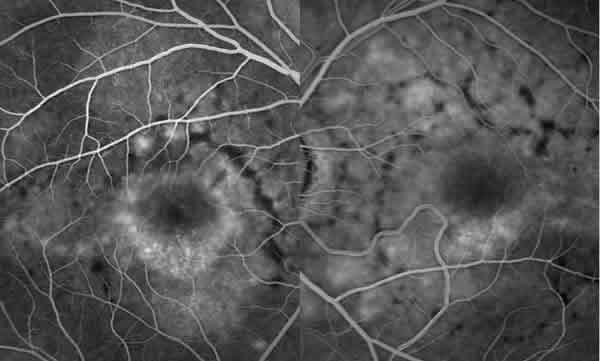

En la angiografía fluoresceínica (AFG) presentaba un patrón anular perimacular de aumento de la fluorescencia coroidea junto con un patrón reticular con efecto pantalla, siendo los flecos hipofluorescentes (figs. 4 y 5).

Fig. 5. AFG de AO del caso 1. Detalle del polo posterior de AO.